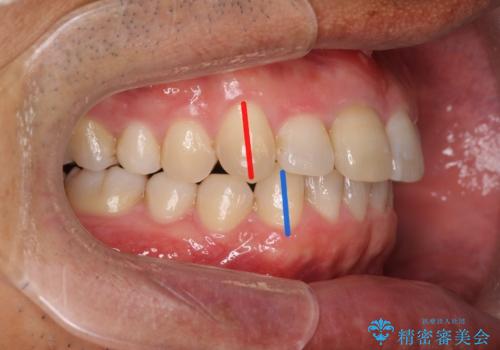

[ マウスピース矯正 ] 出っ歯に見える前歯を改善したい

![[ マウスピース矯正 ] 出っ歯に見える前歯を改善したいの症例 治療前](https://seimitsushinbi.jp/wp/wp-content/uploads/2023/10/IMG_6858-500x350.jpg?v=1697014973)

![[ マウスピース矯正 ] 出っ歯に見える前歯を改善したいの症例 治療後](https://seimitsushinbi.jp/wp/wp-content/uploads/2023/10/8a6c9bf89570c0c75da0a5fabd1cd70e-500x350.jpg?v=1697014858)